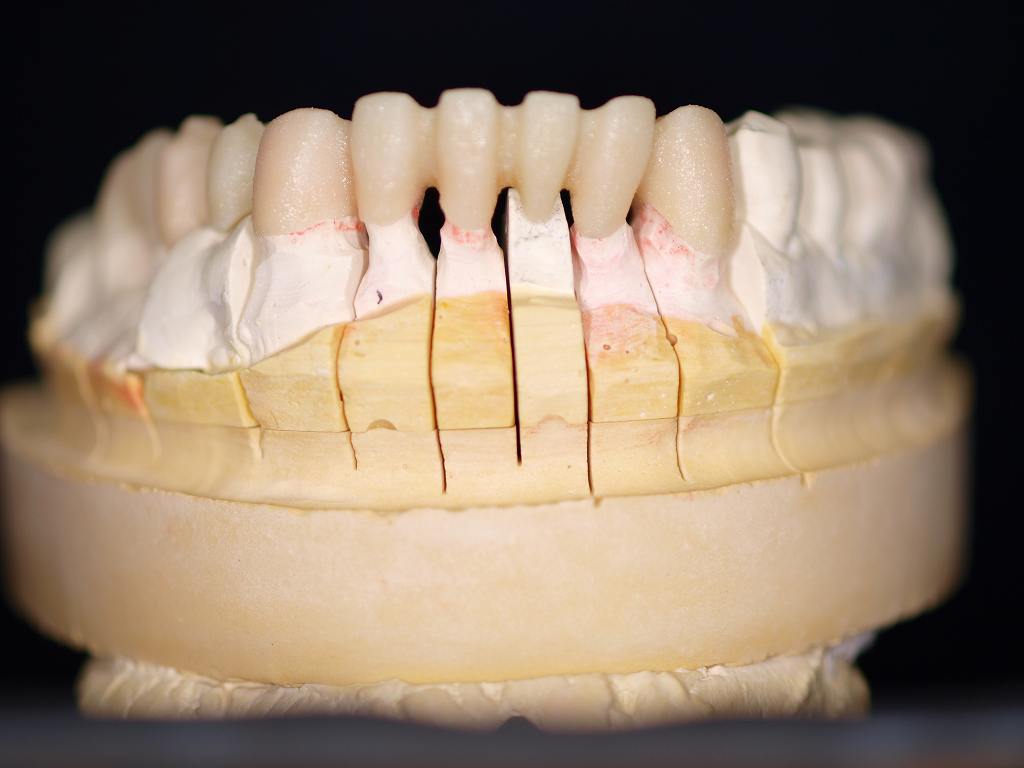

ジルコニアブリッジの7時間半かけてのシンタリング後、模型合わせ、内面調整ポーセレン築造へ 焼成中の画像になります。 焼き上げると青色のポーセレンもこんな色調を作り出していきます。1本8万円|お知らせ |広島市安佐南区の歯科医院

ジルコニアブリッジの7時間半かけてのシンタリング後、模型合わせ、内面調整ポーセレン築造へ 焼成中の画像になります。 焼き上げると青色のポーセレンもこんな色調を作り出していきます。1本8万円

ジルコニアブリッジの7時間半かけてのシンタリング後、模型合わせ、内面調整ポーセレン築造へ 焼成中の画像になります。 焼き上げると青色のポーセレンもこんな色調を作り出していきます。1本8万円